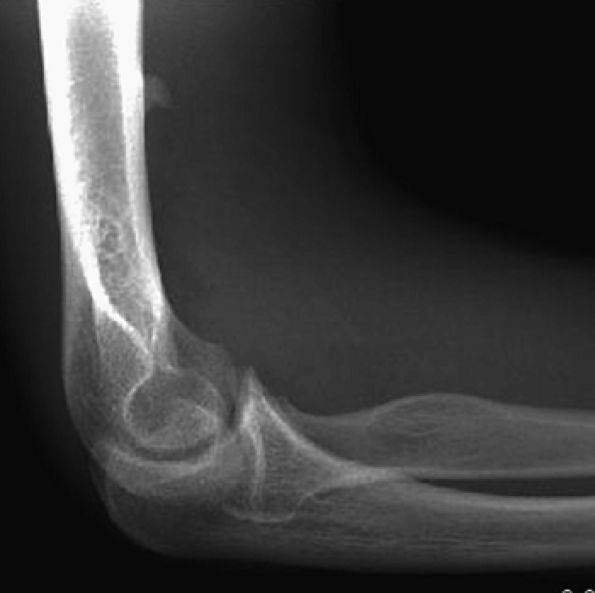

FIGURE 12.29 ● Supracondylar process. Lateral radiograph of the elbow depicts osseous excrescence arising from the anterior aspect of the distal humerus and pointing toward the elbow joint.

|